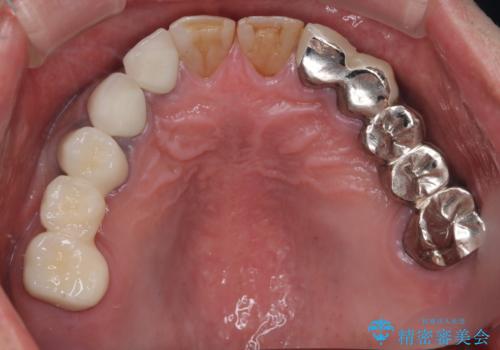

歯肉からの出血 適合の悪い銀歯をオールセラミックのブリッジにやり替え

- 右上奥歯の歯肉から出血があり異和感をおぼえ来院された患者様です。

歯周治療と補綴治療を行いました。

以前の被せ物を除去し、仮歯に変えてすぐに異和感がとれました。

歯周治療を行い、歯肉が引き締まってから補綴治療しました。